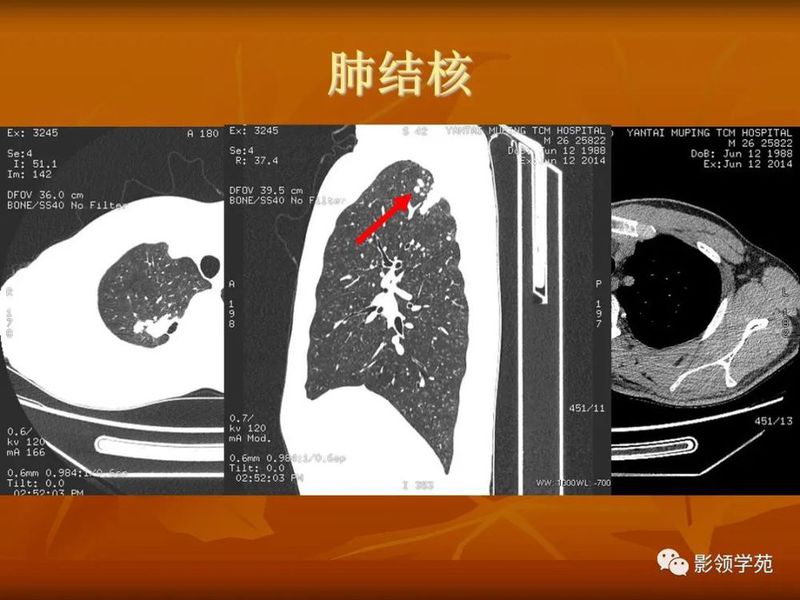

(2)空洞病变发生于双肺上叶尖后段、下叶背段,病变周围可见点状、结节状及片状卫星病灶,洞壁组织无明显强化或有包膜线样强化时,考虑结核;结核球的空洞多位于病变的肺门侧,与引流支气管相同,洞内壁一般较光滑。